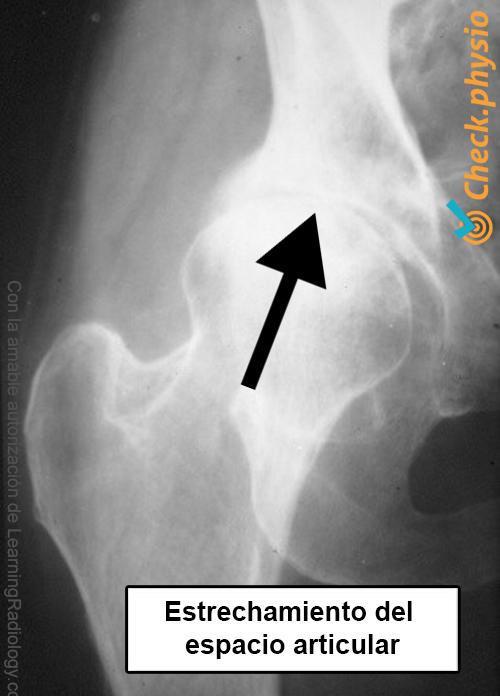

La exploración física en combinación con el relato del paciente suele ser suficiente para establecer el diagnóstico. Solo se hacen radiografías si hay dudas sobre el diagnóstico o si se está considerando la posibilidad de una intervención quirúrgica. En caso de osteoartrosis, el estrechamiento del espacio articular será visible en la radiografía. Además, pueden ser visibles otros efectos de la osteoartrosis, como la formación de osteofitos.

artrosis de cadera radiografía línea articular